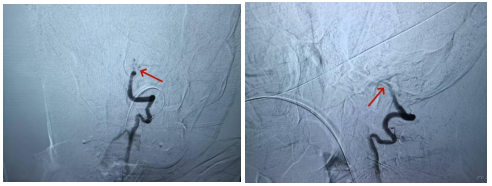

▲术前造影:基底动脉主干闭塞

苏杭立即联系神经内科介入团队组长副主任医师李军连夜赶来医院参加救治。他与苏杭联手,会同一并赶来的医院导管室技师护士们,迅速开展救治工作。在凌晨2点,紧张有序的手术开始了。由于患者高龄,血管迂曲和钙化严重,手术面临诸多困难。但在团队的共同努力下,成功在右侧大脑后动脉及基底动脉闭塞段置入并成功释放取栓支架。5分钟后,待血栓与支架充分缠结,负压吸引下医生们小心翼翼地撤出取栓支架,上面粘附着一条约7mm的暗红色血栓,复查造影,基底动脉成功开通,刘奶奶的生命通道终于被打通了!同时也再次刷新了医院神经内科介入团队为超高龄患者成功进行急诊取栓手术并取得良好预后的记录。

▲术后:基底动脉开通,血栓取出,术后复查核磁